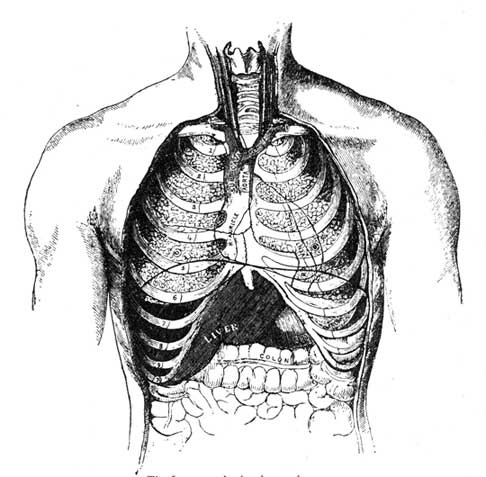

1. Vertebral Column; 2. Skull; 4. Sternum; 7. Collar Bone; 15. Hip Bone; 16. Sacrum; 18. Femur; 19. Knee Pan; 21. Fibula; 22. Tibia; 8. Humerus; 10. Radius; 11. Ulna.